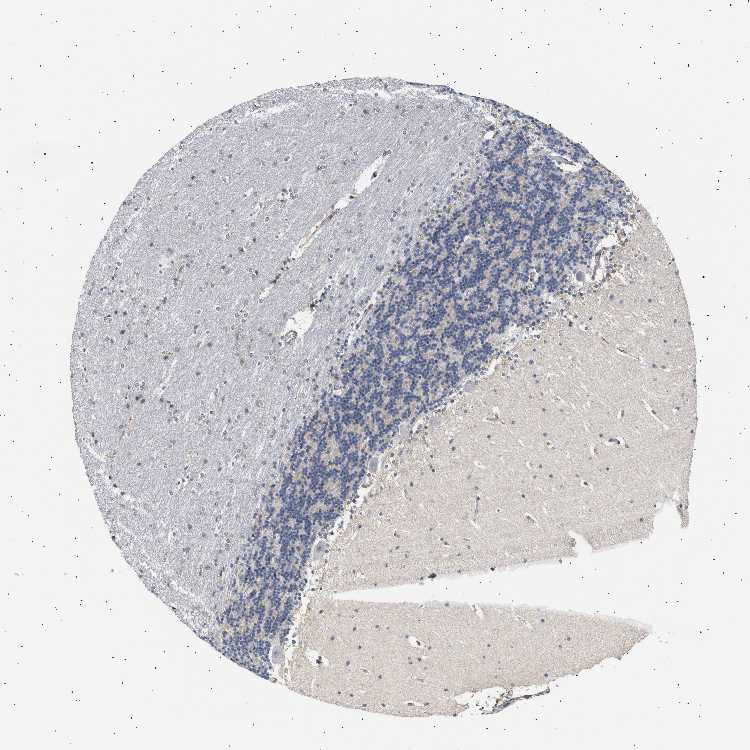

BRAIN CEREBELLUM Show tissue menu

CEREBELLUM - Expression summary

CEREBELLUM - Antibody stainingi

Antibody staining in the annotated cell types in the current human tissue is reported as not detected, low, medium, or high, based on conventional immunohistochemistry profiling in selected tissues. This score is based on the combination of the staining intensity and fraction of stained cells.

Each image is clickable and will lead to virtual microscopy that enables deeper exploration of all samples and also displays staining intensity scores, fraction scores and subcellular localization as well as patient and tissue information for each sample.

Antibody HPA021608

Purkinje cells Not detected

Cells in granular layer Not detected

Cells in molecular layer Not detected